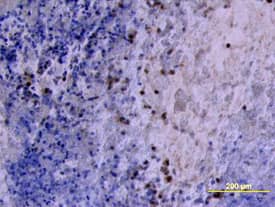

MMP-2 antibody in Human Ovarian Cancer Tissue by Immunohistochemistry (IHC-P).

MMP‑2 in Human Ovarian Cancer Tissue.

MMP-2 was detected in immersion fixed paraffin-embedded sections of human ovarian cancer tissue using Goat Anti-Human MMP-2 Antigen Affinity-purified Poly-clonal Antibody (Catalog # AF902) at 10 µg/mL overnight at 4 °C. Tissue was stained using the Anti-Goat HRP-DAB Cell & Tissue Staining Kit (brown; CTS008) and counter-stained with hematoxylin (blue). View our protocol for Chromogenic IHC Staining of Paraffin-embedded Tissue Sections.